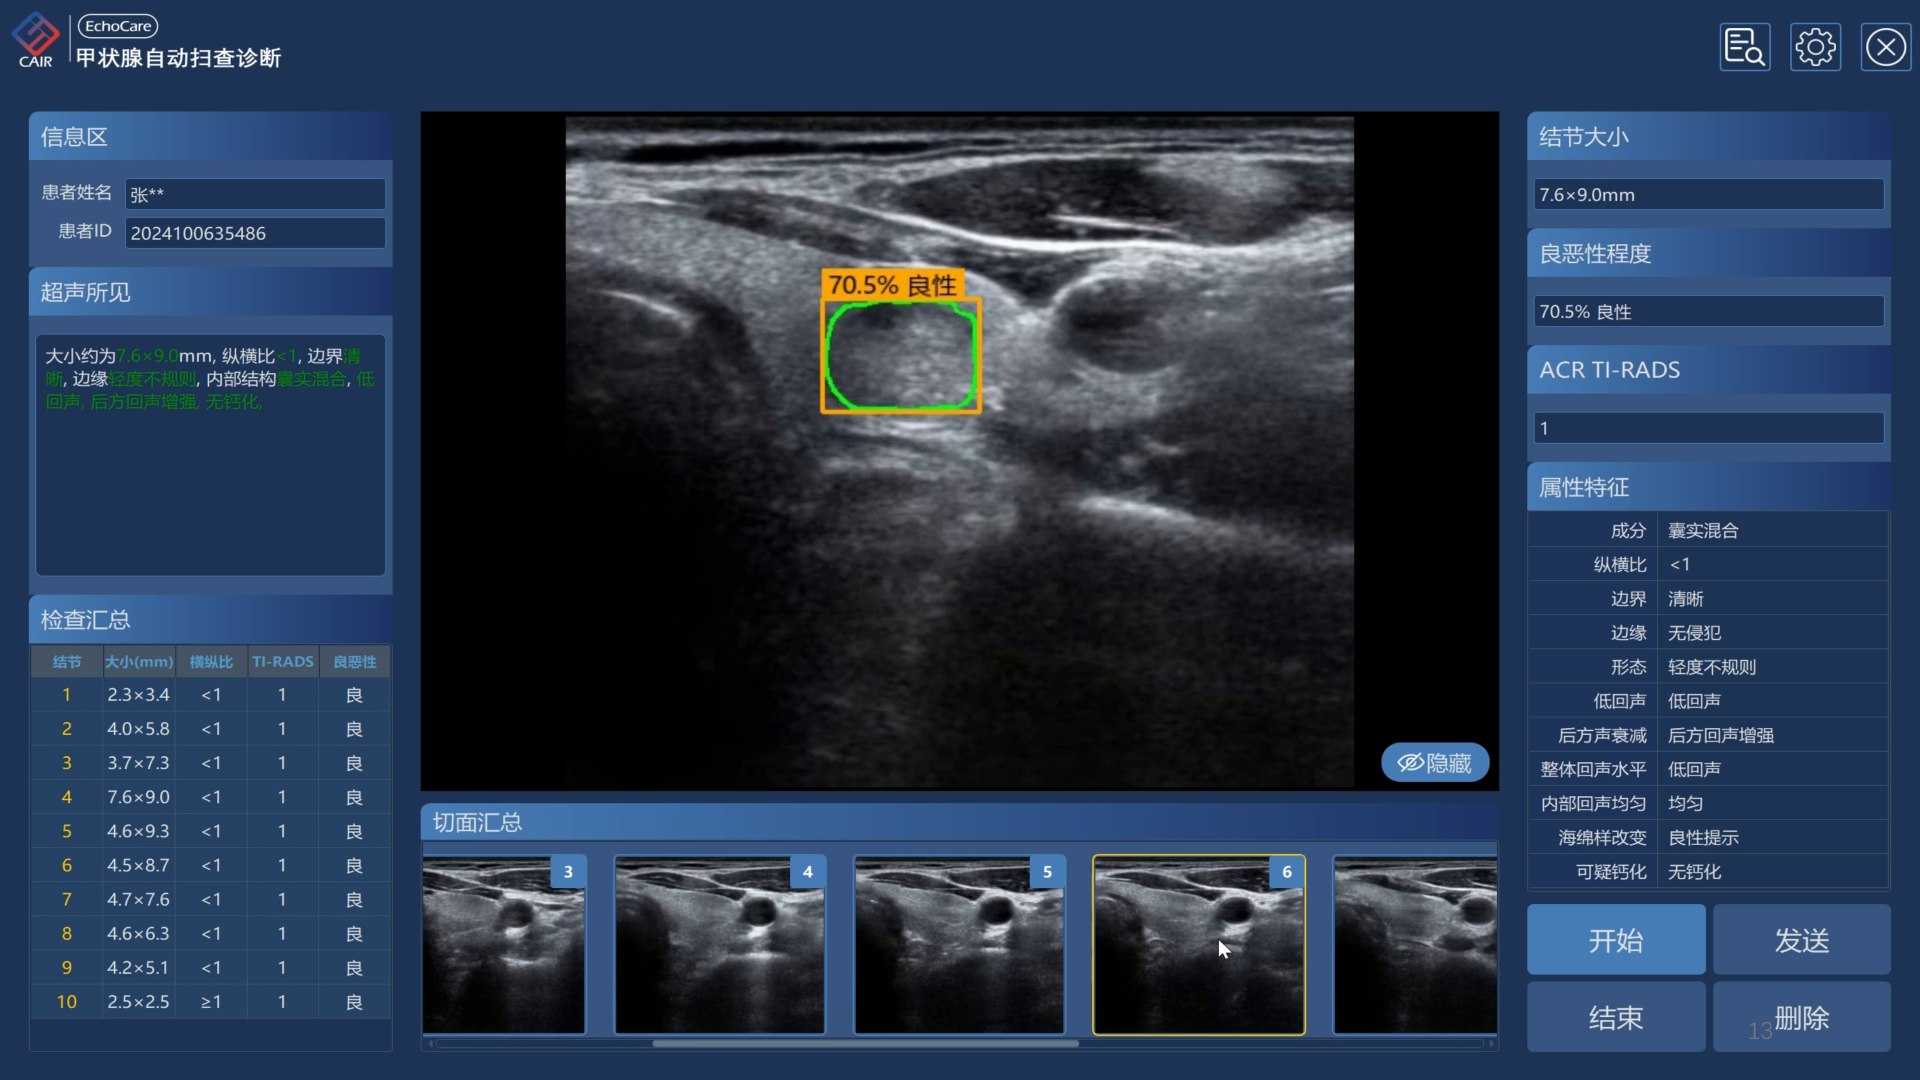

中南大学湘雅医院甲状腺超声检查

甲状腺结节在人群中检出率高达70%以上,其良恶性的早期识别与精准管理至关重要。为解决这一问题,CAIR与中南大学湘雅医院常实主任合作在该医院1000+甲状腺超声检查病例上开展了临床回溯性验证:

- 关键帧识别的准确率89.7%;

- 甲状腺结节检测的平均精度88.8%,相对SOTA方法提升5%以上;

- 结节良恶性分类的分类灵敏度90.5%,特异度达到94.1%。

常实主任表示:“甲状腺超声AI系统通过对结节的影像特征进行智能识别与量化分析,可有效减少人为差异,提升检出效率与分类一致性,为早期诊断与个体化治疗决策提供可靠支持。该系统可以促进甲状腺结节的分级诊疗,优化并节约相关医疗成本。”